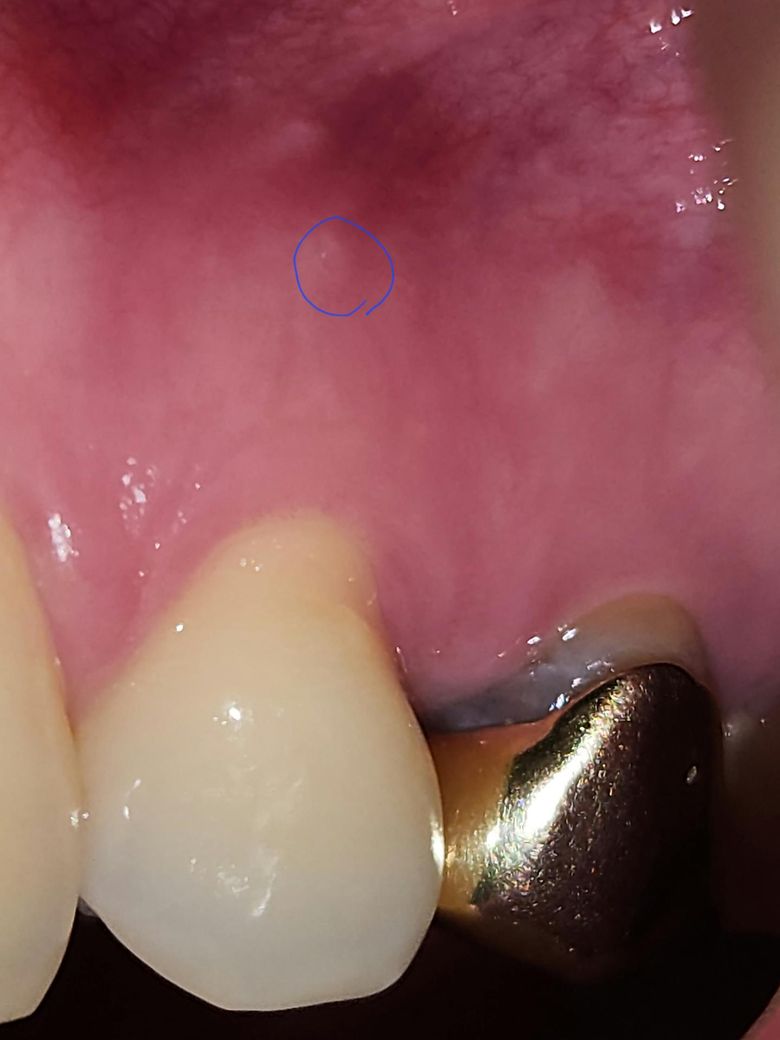

이거 동그라미 친 부분이 치주농양이고 주위에 고름같은게 있나요???

안녕하세요.. 제가 몇일전부터 혀에 해당 동그라미 사진 갖다대면 좀 볼록한듯한 느낌이 듭니다.

이거 치주농양인가요???

그리고 주위에 농양같은게 있나요????

• 2번 째 사진